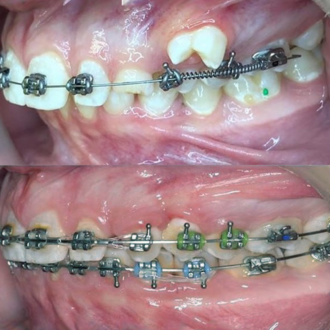

Результат коррекции металлической брекет-системой

Результат коррекции самолигирующей брекет-системой

Результат коррекции элайнерами

Результат коррекции керамической брекет-системой